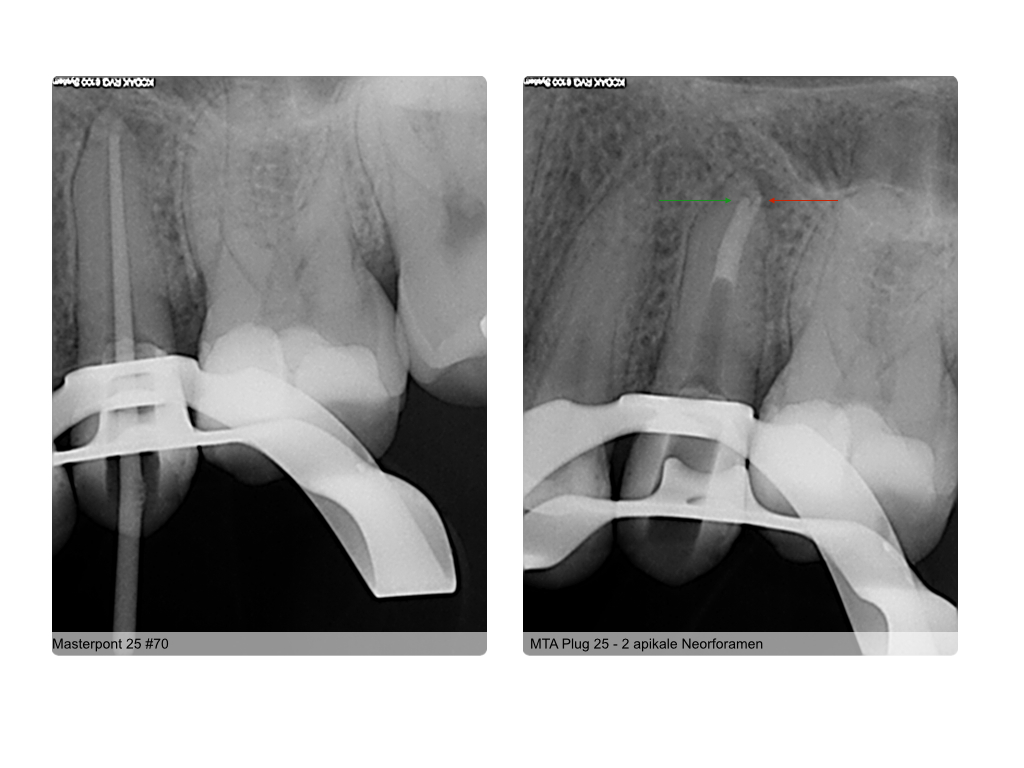

WS11.005 Veröffentlicht 11. November 2014 am 1024 × 768 in Fragestellung: Parodontitis apicalis? (3) Röntgenkontrollen